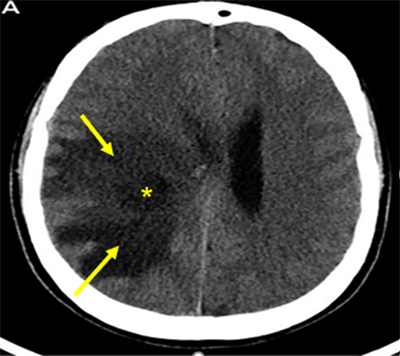

Chẩn đoán và điều trị phù não do khối u nội sọ Ngày đăng: 22/01/2024 Định nghĩa: Phù não là sự tích tụ bất thường nước và dịch trong khu vực tế bào và/hoặc khu vực ngoài tế bào não, dẫn đến sự tăng thể tích toàn bộ não. Phù não do các nguyên nhân khác nhau có cơ chế...